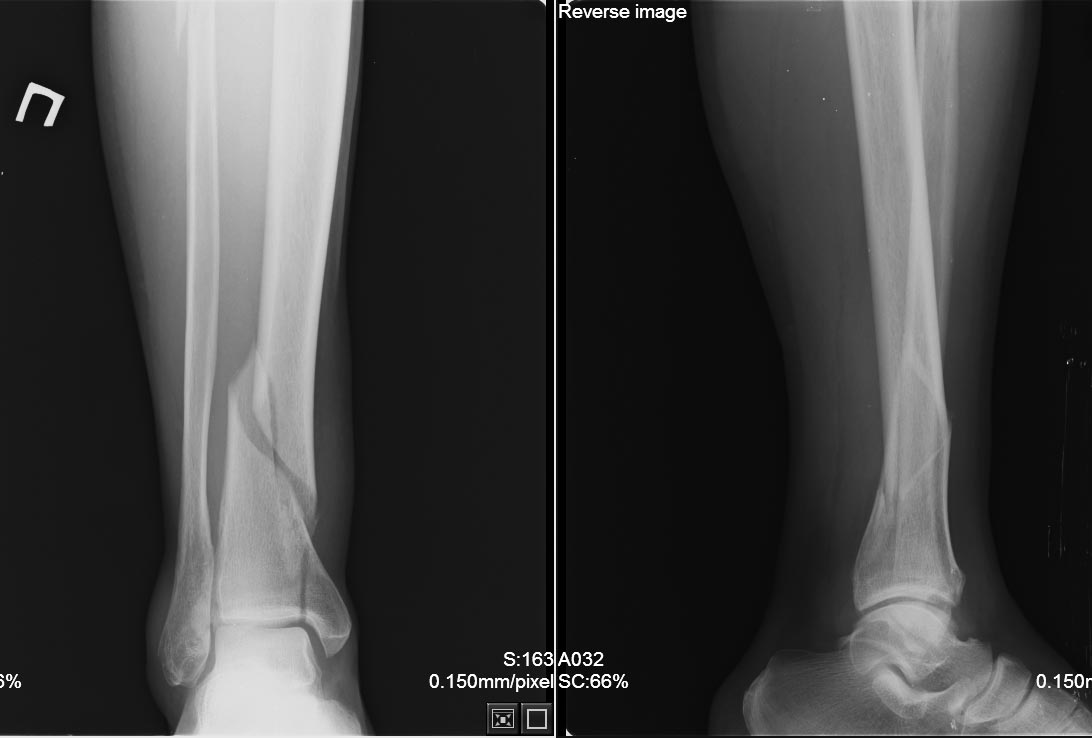

Привожу снимки после операции

Вполне достойно выполнено, абсолютная стабильность. Я правда вчера абсолютно идентичный перелом синтезировал ETN, а медиальную лодыжку из проколов двумя маллеолярными винтами

Стабильность то абсолютная, только какие тут преимущество от пластины с угловой стабильностью? Разве что- цена?

При ранней нагрузке, сломается пластина на уровне 5 винта сверху (: (Уже ломалась)